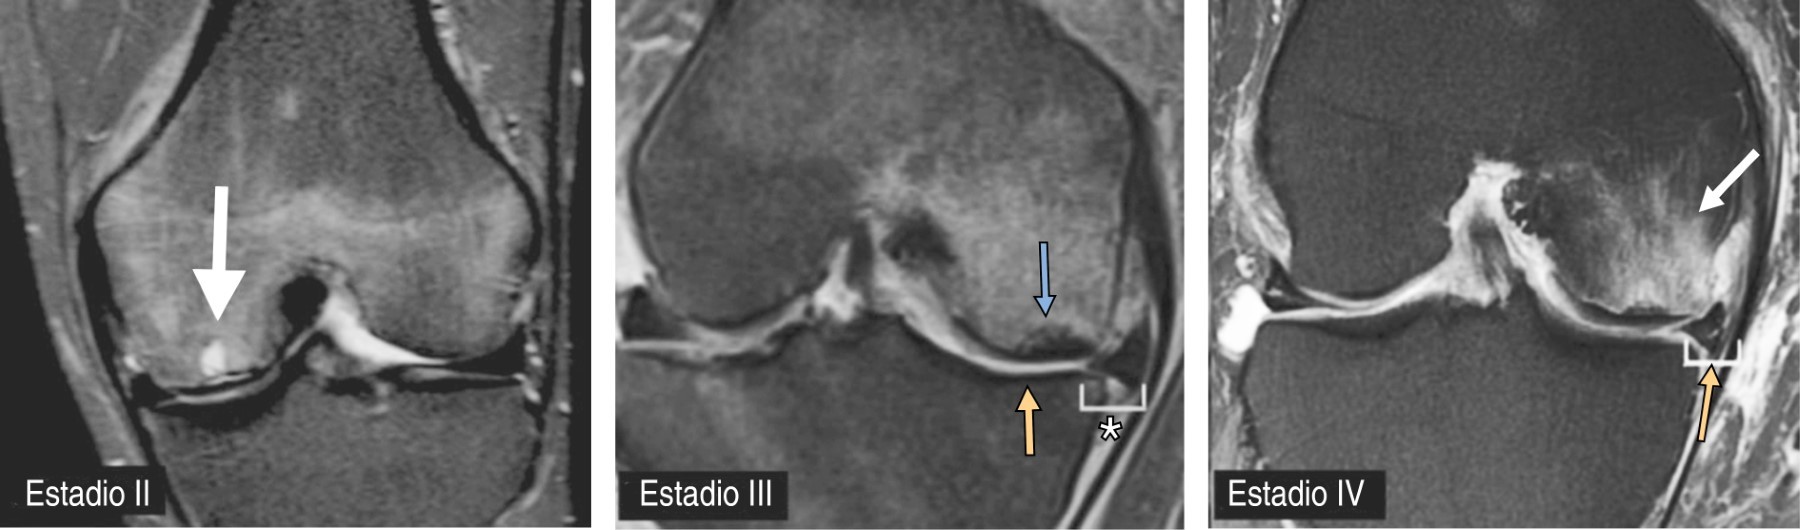

La resonancia magnética es el estándar de oro, siendo valiosa en las primeras fases de la enfermedad, ya que tiene una alta sensibilidad para detectar el edema óseo. Los hallazgos iniciales de la resonancia magnética suelen mostrar un edema de médula ósea localizado en el cóndilo femoral medial, junto con una semiluna subcondral o una zona lineal de baja intensidad de señal en las secuencias ponderadas en T1 y T2. Esta región se localiza en la parte central del cóndilo femoral que soporta el peso, mientras que el cartílago articular, situado por encima, permanece intacto. A medida que la enfermedad progresa a la fase de colapso óseo subcondral, la resonancia magnética revela depresiones focales en el contorno de la epífisis y una línea de fractura infiltrada por líquido subcondral. Además, con frecuencia se observan desgarros meniscales concomitantes (Figura 2).23-25

La osteonecrosis de rodilla puede estadificarse para evaluar su gravedad y orientar el tratamiento. En 1979, Koshino desarrolló una clasificación para la osteonecrosis espontánea de la rodilla que actualmente se utiliza para todos los tipos. Consta de cuatro estadios (Tabla 1). El estadio I es el de un paciente con síntomas en la rodilla, pero radiografías normales. El estadio II consiste en un aplanamiento de los cóndilos y radiografías subcondrales sin colapso. En el estadio III hay colapso subcondral, mientras que el estadio IV consiste en más cambios degenerativos asociados a la osteoartrosis.26,27

Otra clasificación utilizada es el sistema de estadificación modificado de Ficat y Arlet adaptado para la rodilla a partir de la versión original que describe la osteonecrosis de la cabeza femoral (Figura 3). Este sistema se basa en los hallazgos radiológicos. En la etapa I, los pacientes presentan hallazgos radiográficos normales. En la etapa II, se observan lesiones quísticas u osteoescleróticas con un contorno normal de la parte distal del fémur, mientras que en la etapa III se detecta un signo de media luna o colapso óseo subcondral. La etapa IV se caracteriza por cambios osteoartríticos.28,29

Figura 2